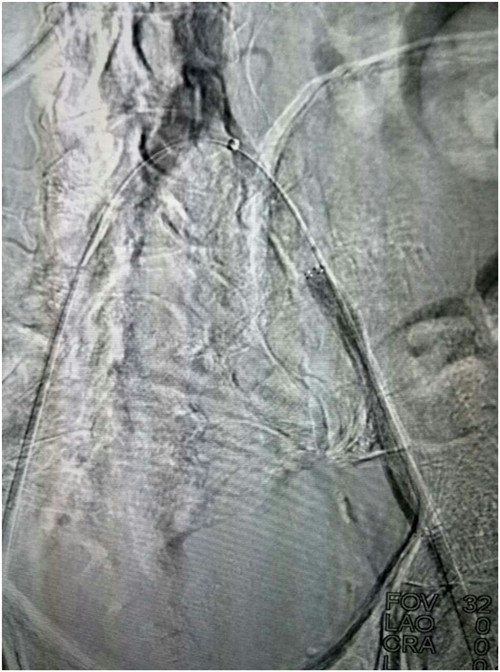

经术前1周精心准备,在科室陈熹主任的统筹协调下,于4月25日下午局麻下在我院介入手术室由普外科马建仓副教授,李宗禹医师在介入室张尚军主管技师配合下完成了普外科首例髂股动脉长段闭塞球囊扩张、支架植入术。术中造影证实左侧髂股动脉闭塞,通过翻山技术从右侧股动脉穿刺入路,导丝顺利通过狭窄病变,球囊扩张后,置入网状支架,使得血管通畅。术后给予双抗,患者静息痛明显改善,换药创面分泌物明显减少,休息明显好转。患者现在正在平稳恢复中。